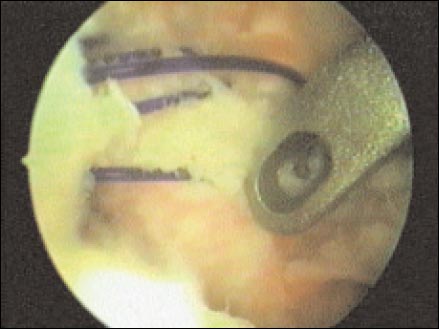

Los anclajes óseos son colocados en la unión oteocartilaginosa (Fig. 5) sobre el cartílago en tres puntos, aproximadamente correspondiente a horas 5, 4 y 2 (hombro derecho), dependiendo de la lesión; realizamos la toma capsular y del rodete con Ethibond Nº. 2, el pasaje de los hilos requiere de un “shutter-relay” o otros tipos de pasa-suturas. Utilizamos nudos deslizantes o no deslizantes según necesidad y, un empujanudos para llevar las estructuras capsulo-ligamentarias al sitio deseado.(Fig. 6). Con ambas técnicas realizamos plicaturas capsulares con los mismos puntos de la sutura transglenoidea o los anclajes óseos.

Figura 6: sutura con ancllajes oseos